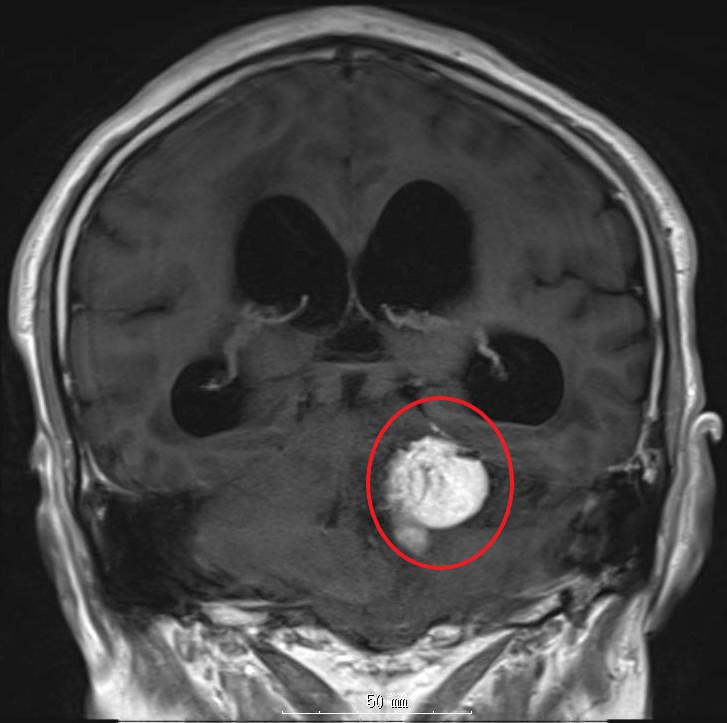

松果体近傍部腫瘍

松果体近傍部腫瘍は小脳テントを経て病変部にアプローチするのが主流です。この症例も同アプローチにて摘出しました。

術前MRI画像